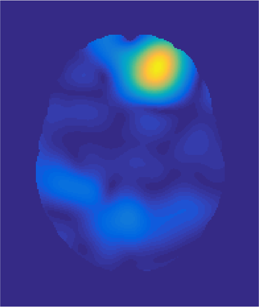

(a) (b) (c) (d) (e)

Fig. 3: Example atlas-to-image registration errors [mm]: (a) tumor; (b) LRS; (c) PCA model w/o regularization; (d) PCA model w/ one step of regularization; (e) PCA model w/ two steps of regularization.

Fig. 2 shows atlas-to-image registration results for images with and without tumor, LRS reconstruction and our PCA-based models with and without regularization. Fig. 3 shows the spatial error distributions, compared to the ground truth registration. We use NiftyReg [17] (with standard settings) and NCC for registrations. Errors are computed using Euclidean distance. Direct registration of the tumor image results in large registration errors. Registration to the low-rank reconstruction greatly reduces the error in the tumor areas but retains errors near the cortex, mainly due to its blurry reconstruction. Our PCA models further reduce registration errors in the tumor areas and keep errors near the cortex low.